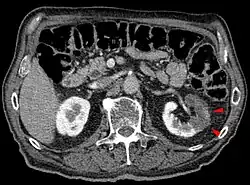

Infarkt ledviny

Infarkty ledviny mají na řezu tvar trojúhelníku, v jehož vrcholu leží uzavřená přívodná tepna.[3] Ložisko má bílou nebo nažloutlou barvu.[3]